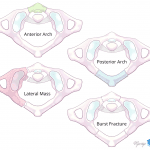

- Acute comminuted C1 burst fracture (Jefferson fracture) with fracture lines extending through the anterior arch, right lateral mass, and both lamina. On the right, the fracture extends into the C1-C2 articulation with associated asymmetric widening

- Jefferson fracture

Acute comminuted C1 burst fracture (Jefferson fracture) with fracture lines extending through the anterior arch, right lateral mass, and both lamina. On the right, the fracture extends into the C1-C2 articulation with associated asymmetric widening. Lateral masses of C1 still articulate with the occipital condyles. Consider MRI to further assess for ligamentous injury.